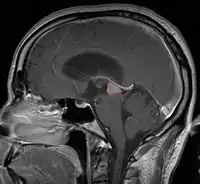

Pineal Gland Tumors

Clinical Presentation

- Determined by the spatial anatomy and direction of growth

- Obstruction of aquaduct: hydrocephalus presenting as headaches, nausea, vomiting

- Compromise of superior colliculus: vertical gaze palsy, pupillary and oculomotor nerve paresis (Parinaud syndrome)

- Progressive growth: cranial nerve neuropathies, hypothalamic dysfunction

- Work-up includes MRI, CSF, serum markers for bHCG and AFP

- Usually well-circumscribed, large lesions, sometimes with cystic component